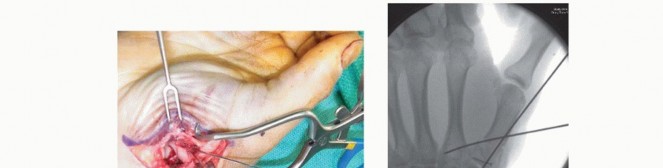

Closed Reduction and Percutaneous Pinning (CRPP)

CRPP is the treatment of choice for classic Bennett fractures where the volar-ulnar fragment is too small to reliably accept a lag screw, yet the joint can be anatomically reduced closed. The reduction maneuver is highly specific, designed to counteract the deforming forces of the APL and Adductor Pollicis. Longitudinal traction is applied to the thumb, followed by palmar abduction and pronation. Direct pressure is then applied to the dorsal-radial aspect of the metacarpal base, effectively pushing the shaft back into the anatomic cradle of the intact volar-ulnar fragment.

Once anatomic reduction is confirmed via multi-planar fluoroscopy, percutaneous fixation is achieved. Typically, two 0.045-inch or 0.062-inch Kirschner wires are utilized. The first wire is driven from the dorsal-radial aspect of the metacarpal shaft directly into the trapezium, effectively neutralizing the proximal pull of the APL. A second wire is often placed transversely from the first metacarpal shaft into the second metacarpal to control rotation and maintain the web space. Pins are cut outside the skin and capped to facilitate easy removal in the clinic.

Open Reduction and Internal Fixation (ORIF) - Wagner Approach

For fractures with large volar-ulnar fragments (>20% of the articular surface), displaced Rolando fractures, or cases where closed reduction fails, ORIF is unequivocally mandated. The classic Wagner approach provides unparalleled exposure to the thumb CMC joint. A curvilinear incision is made along the glabrous border of the thenar eminence, curving dorsally at the level of the CMC joint.

Meticulous superficial dissection is required to identify and protect the sensory branches of the superficial radial nerve dorsally and the palmar cutaneous branch of the median nerve volarly. The thenar musculature (abductor pollicis brevis and opponens pollicis) is sharply elevated from the metacarpal shaft and retracted volarly. The joint capsule is then incised longitudinally or in an L-shaped fashion to expose the articular surface. The hematoma is evacuated, and the fracture fragments are meticulously debrided of interposed soft tissue.

For a large fragment Bennett fracture, the shaft is reduced to the volar-ulnar fragment using a pointed reduction clamp. Provisional fixation is achieved with a K-wire. A 1.5mm or 2.0mm lag screw is then placed perpendicular to the fracture plane. The near cortex must be overdrilled (gliding hole) and the far cortex underdrilled (thread hole) to achieve true interfragmentary compression. The screw head should be countersunk to prevent hardware prominence beneath the thenar muscles.